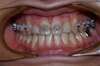

Intra Orale Face